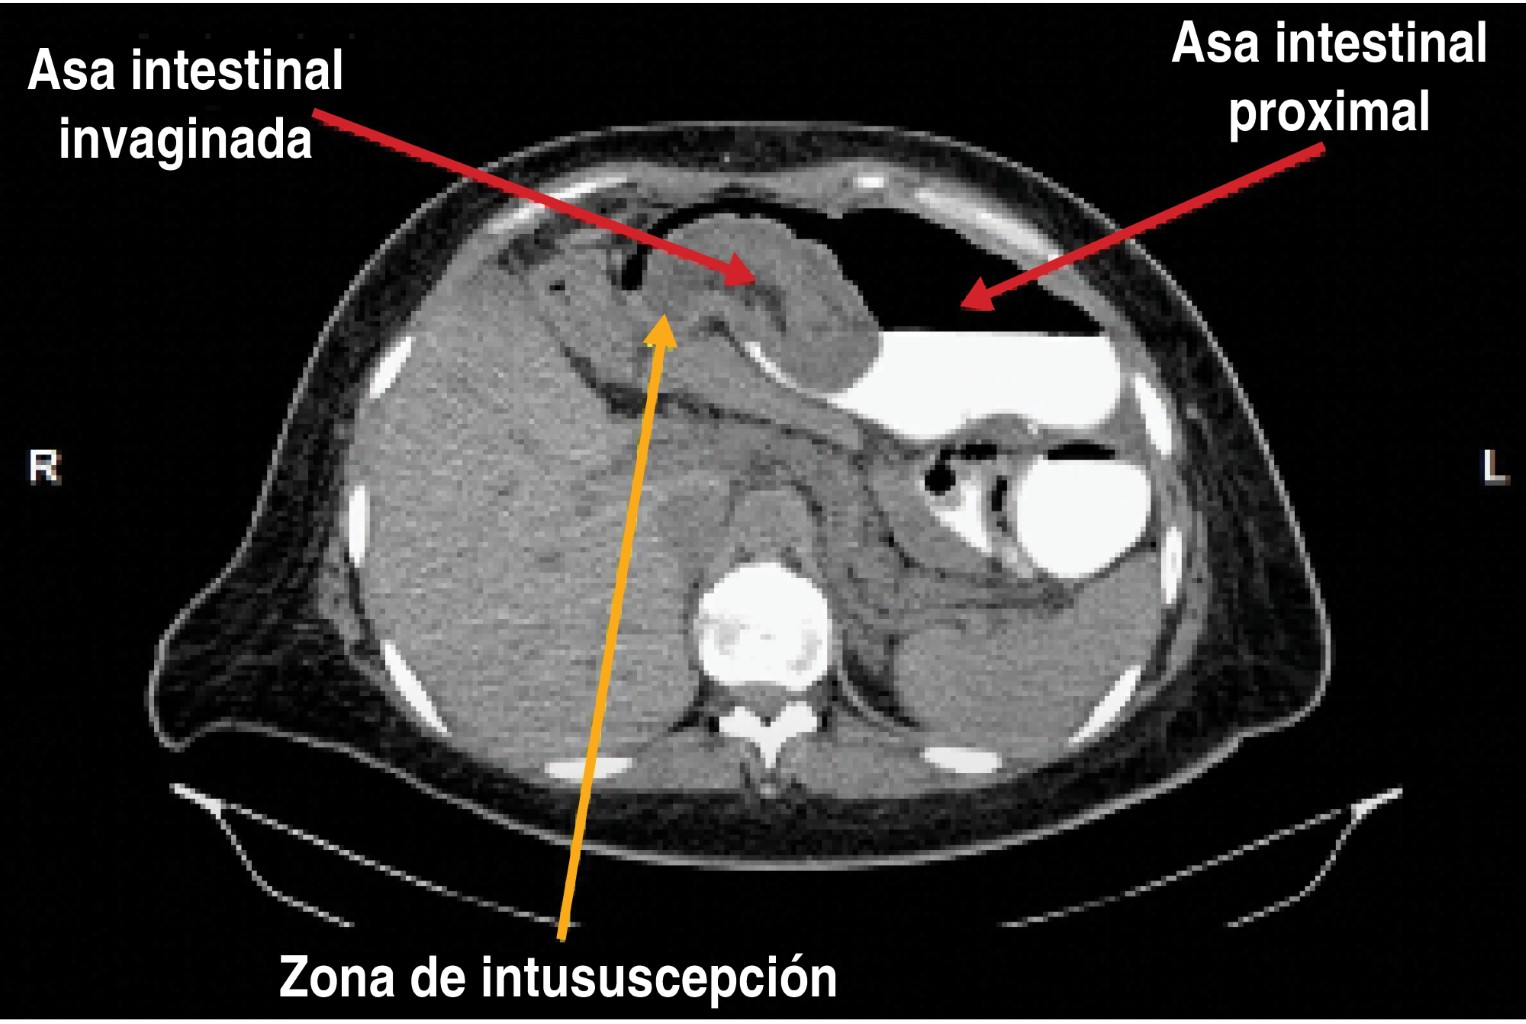

Introduction: the most common cause of intestinal obstruction after Roux-en-Y gastric bypass (RYGB) is internal herniation and can be resolved by laparoscopic approach. The objective of this paper is to present three unusual causes of intestinal obstruction in bariatric patients that can be resolved by a minimally invasive approach. Report of cases: The first case presents a 31-year-old patient with a history of Roux-en-Y gastric bypass 3 years previously who presented with an occlusive syndrome. An intussusception was diagnosed and successfully managed with laparoscopy. The second case is a 37-year-old patient who had a gastric balloon placed 1 year prior to admission, who did not attend withdrawal at 6 months, goes to the hospital with an occlusive picture, diagnosing distal impaction of the balloon, which was successfully extracted laparoscopic route. Last case, a 39-year-old patient with a history of Roux-en-Y gastric bypass 9 years prior to admission with occlusive syndrome. Laparoscopy revealed an 8 cm impacted phytobezoar in the terminal ileum. It was manually removed using a 5 cm disposable retractor through the umbilicus. Results: two cases were successfully resolved laparoscopically and the third was extracted extracorporeally, but with a laparoscopic approach. No patient presented early or late complications. Conclusions: the causes of intestinal obstruction in this series of bariatric cases are unusual and all could be resolved by minimal invasion with no mortality to report.

Figure 3

Figure 4